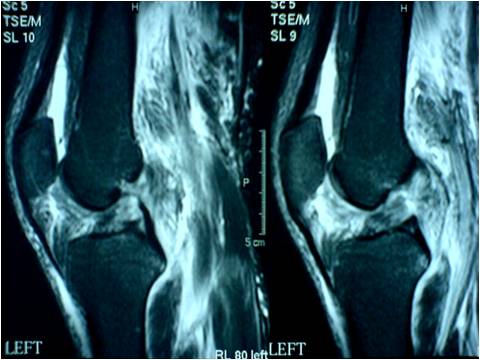

MRI KNEE